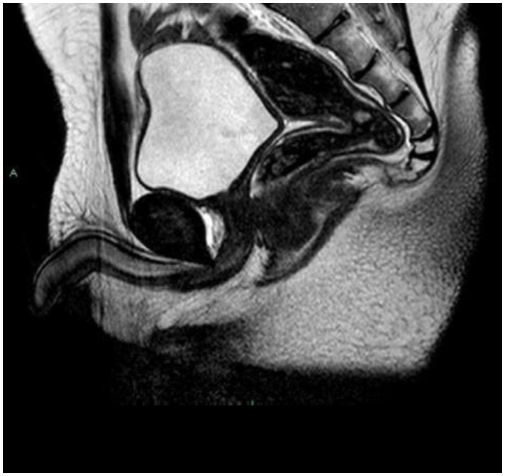

MRI confirmed absent scrotum, testicles, epididymis, prostate gland and seminal vesicles. Furthermore, MRI showed absent corpus spongiosum with normal corpus cavernosum”. Bladder and urethra were normally detectable.

No images compatible with undescended testicles were evident (Figures 1,2 and 3) Subsequently the patient underwent karyotype analysis showing an XY profile.

| Absence of spongy body of urethra, with Absence of corpus spongiosum, with normal corpus

cavernousum. MRI confirmed the absent scrotum sac, testicles, epididymis and related spermatic cords.

Normal representation of bladder- urethral junction. Normal representation of remaining pelvic organs. Figure 1: Sagittal T2-weighted image of pelvic district |

| No images compatible with undescended testicles are evident. Figure 2: Figure 2: Axial T2- weighted image of the pelvic district |

| Prostate gland and seminal vesicles are not evident. Figure 3: Coronal T2 weighted image of pelvic district |